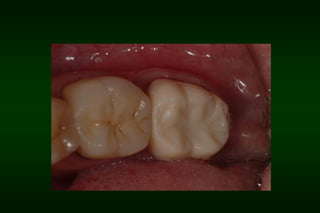

Types of Provisional Restoration II.Customized resin restorations 1. Direct technique b. Direct custom-carved (block-temporary)